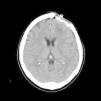

El Pott's puffy tumor (PPT) es una rara entidad que en la actualidad representa un abombamiento del cuero cabelludo asociado a un absceso subperióstico y a una osteomielitis craneal, pudiendo acompañarse o no de infección intracraneal. Suele asociarse a la sinusitis frontal, tratándose de una complicación típica, aunque poco frecuente de la misma. Por su parte las osteomielitis causadas por Actinomyces son raras y suelen tener lugar a nivel mandibular, no encontrándose apenas casos de osteomielitis craneal causada por este género bacteriano, en especial tras traumatismo craneoencefálico. Presentamos un caso especialmente poco usual al tratarse de un PPT frontal tras traumatismo cerrado, con componente intracraneal y en el que tras cirugía se aisló Actinomyces como copartícipe de dicha infección, junto con Fusobacterium y Propionibacterium.

Pott's puffy tumour (PPT) is a rare entity that involves scalp swelling associated with subperiosteal abscess and cranial osteomyelitis, occasionally accompanied by intracranial infection. It is usually affiliated with frontal sinusitis, which is a typical but infrequent complication. On the contrary, Osteomyelitis by Actinomyces is rare and usually occurs at the mandibular level, with very few cases of cranial osteomyelitis caused by this bacterial specie, especially after traumatic brain injury. We report an exceptionally unusual case of a PPT frontal tumor after blunt trauma (closed head injury), with an intracranial lesion whereby Actinomyces was isolated after surgery, as a co-participant of the mentioned infection besides Fusobacterium and Propionibacterium.